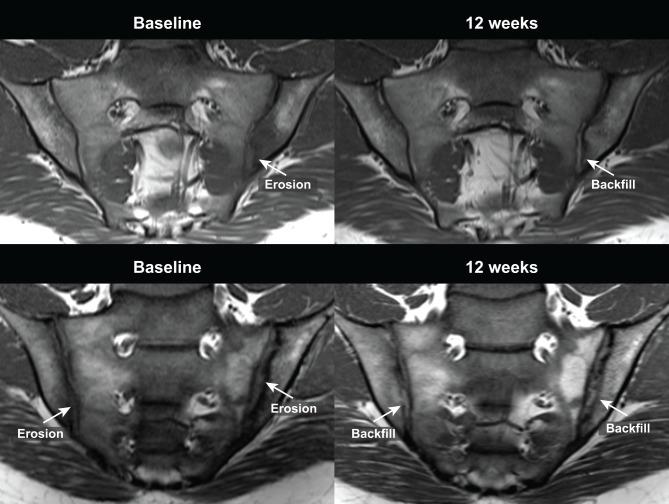

Patients were randomised to double-blind etanercept 50 mg/week or placebo for 12 weeks. Structural lesions at baseline and 12 weeks were scored by two independent readers using the Spondyloarthritis Research Consortium of Canada (SPARCC) SIJ structural score (SSS) on T1-weighted MRI. Change in SPARCC SSS and correlation with improvement in clinical outcomes was evaluated.

MRI scans from 185 patients (etanercept, n=88; placebo, n=97) were reviewed. At baseline, there were no significant differences in mean SPARCC SSS between etanercept and placebo. From baseline to 12 weeks, change in mean SPARCC SSS was significantly greater for etanercept than placebo for erosion (-0.57 vs -0.08, respectively, adjusted p value=0.017) and backfill (0.36 vs 0.06, adjusted p value=0.022). A treatment difference was also present for the subgroup of patients with SIJ inflammation on MRI (SPARCC bone marrow oedema ≥2): erosion: -0.81 versus -0.13 for etanercept versus placebo, respectively, p=0.007; backfill: 0.48 versus 0.08, respectively, p=0.032. Decrease in erosion and increase in backfill correlated with improvement in more clinical outcomes for etanercept than placebo.

Treatment with etanercept was associated with significantly greater reduction in erosions and increase in backfill at 12 weeks compared with placebo, consistent with a very early reparative response to antitumour necrosis factor therapy. The impact on disease progression in spondyloarthritis should be studied further.